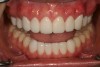

Because the porcelain veneer preparations (teeth No. 3 through No. 14; teeth No. 22 through No. 27) and esthetic temporization (Luxatemp Ultra, DMG America, www.dmg-america.com) were completed on the day of the surgery, the patient was able determine and articulate her esthetic and functional goals after one appointment (Figure 22 through Figure 24). Through minimally invasive comprehensive dentistry, we are able to use creativity to modernize a traditional approach to comprehensive dental treatment. Because of the minimally invasive nature of these modern dental plans, this approach is well liked and easily accepted by patients (Figure 25).